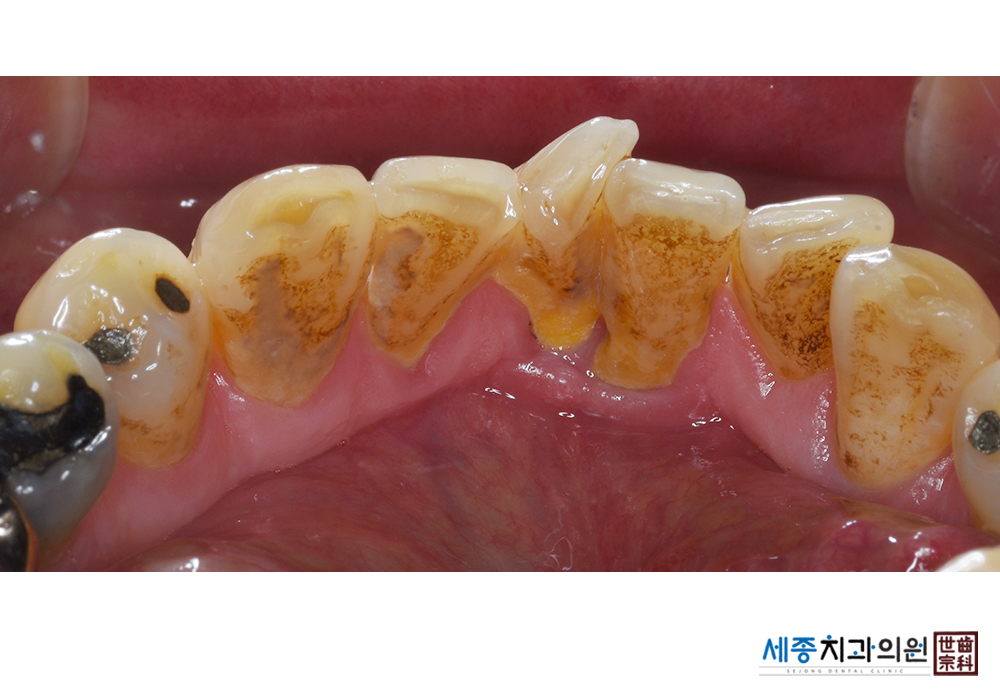

[스케일링] 치주질환 예방 스케일링

치료전 : 2021-03-08

치료후 : 2021-03-08

가글마취&저주파 스켈러를 사용한 스케일링